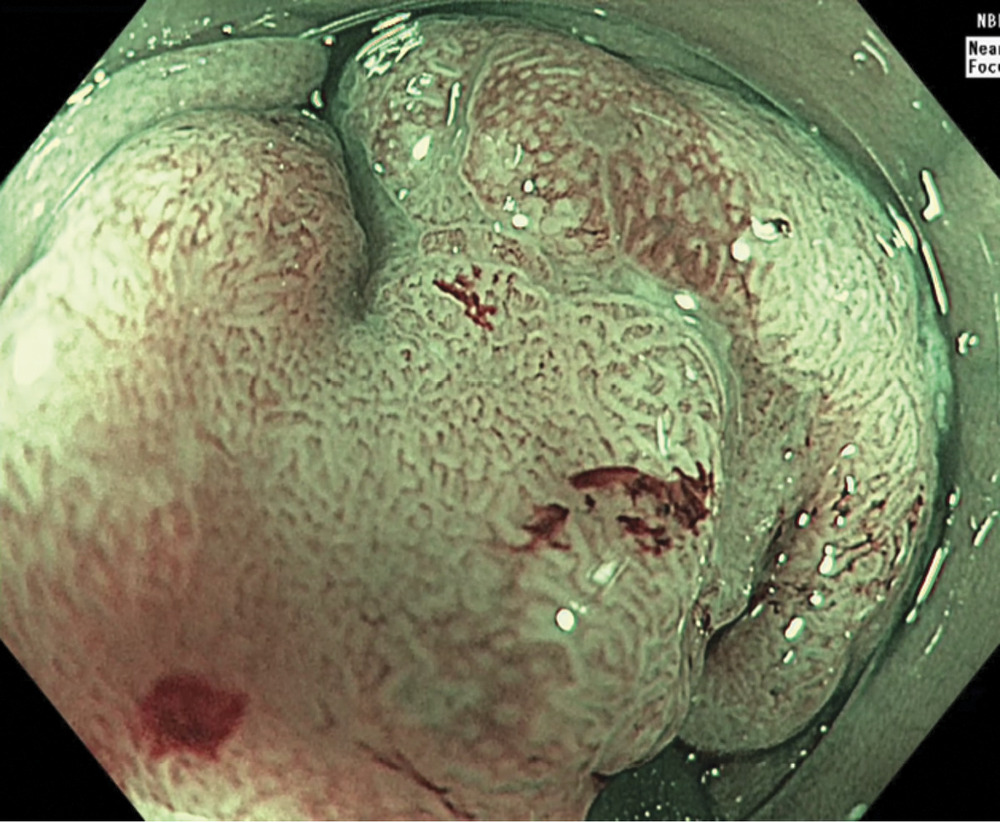

Пациентка К., 59 лет. Диагноз: рак сигмовидной кишки T1N0M0, 1-я стадия, 2-я клиническая группа. При обследовании пациентки в проксимальной части сигмовидной кишки выявлена полиповидная эпителиальная опухоль размером 2,5×2,0 см (рис. 1)

Исследование выполнялось при помощи видеоколоноскопа CF-HQ190L производства «Olympus» (Токио, Япония) и процессора серии EVIS Exera III. Эта система последнего поколения оснащена узкоспектральным режимом (NBI) и функцией увеличения изображения Near focus, которая позволяет выбрать нужную глубину резкости и получить более детализированное изображение слизистой оболочки и капиллярных сетей (рис. 3).